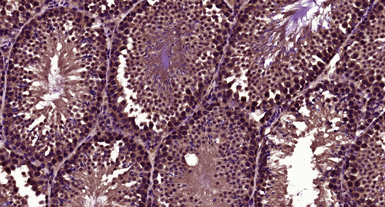

IHC-P analysis of mouse testis tissue using GTX60263 LBX1 antibody.

Antigen retrieval : Boiling in sodium citrate buffer (pH6) for 15min

Dilution : 1:400